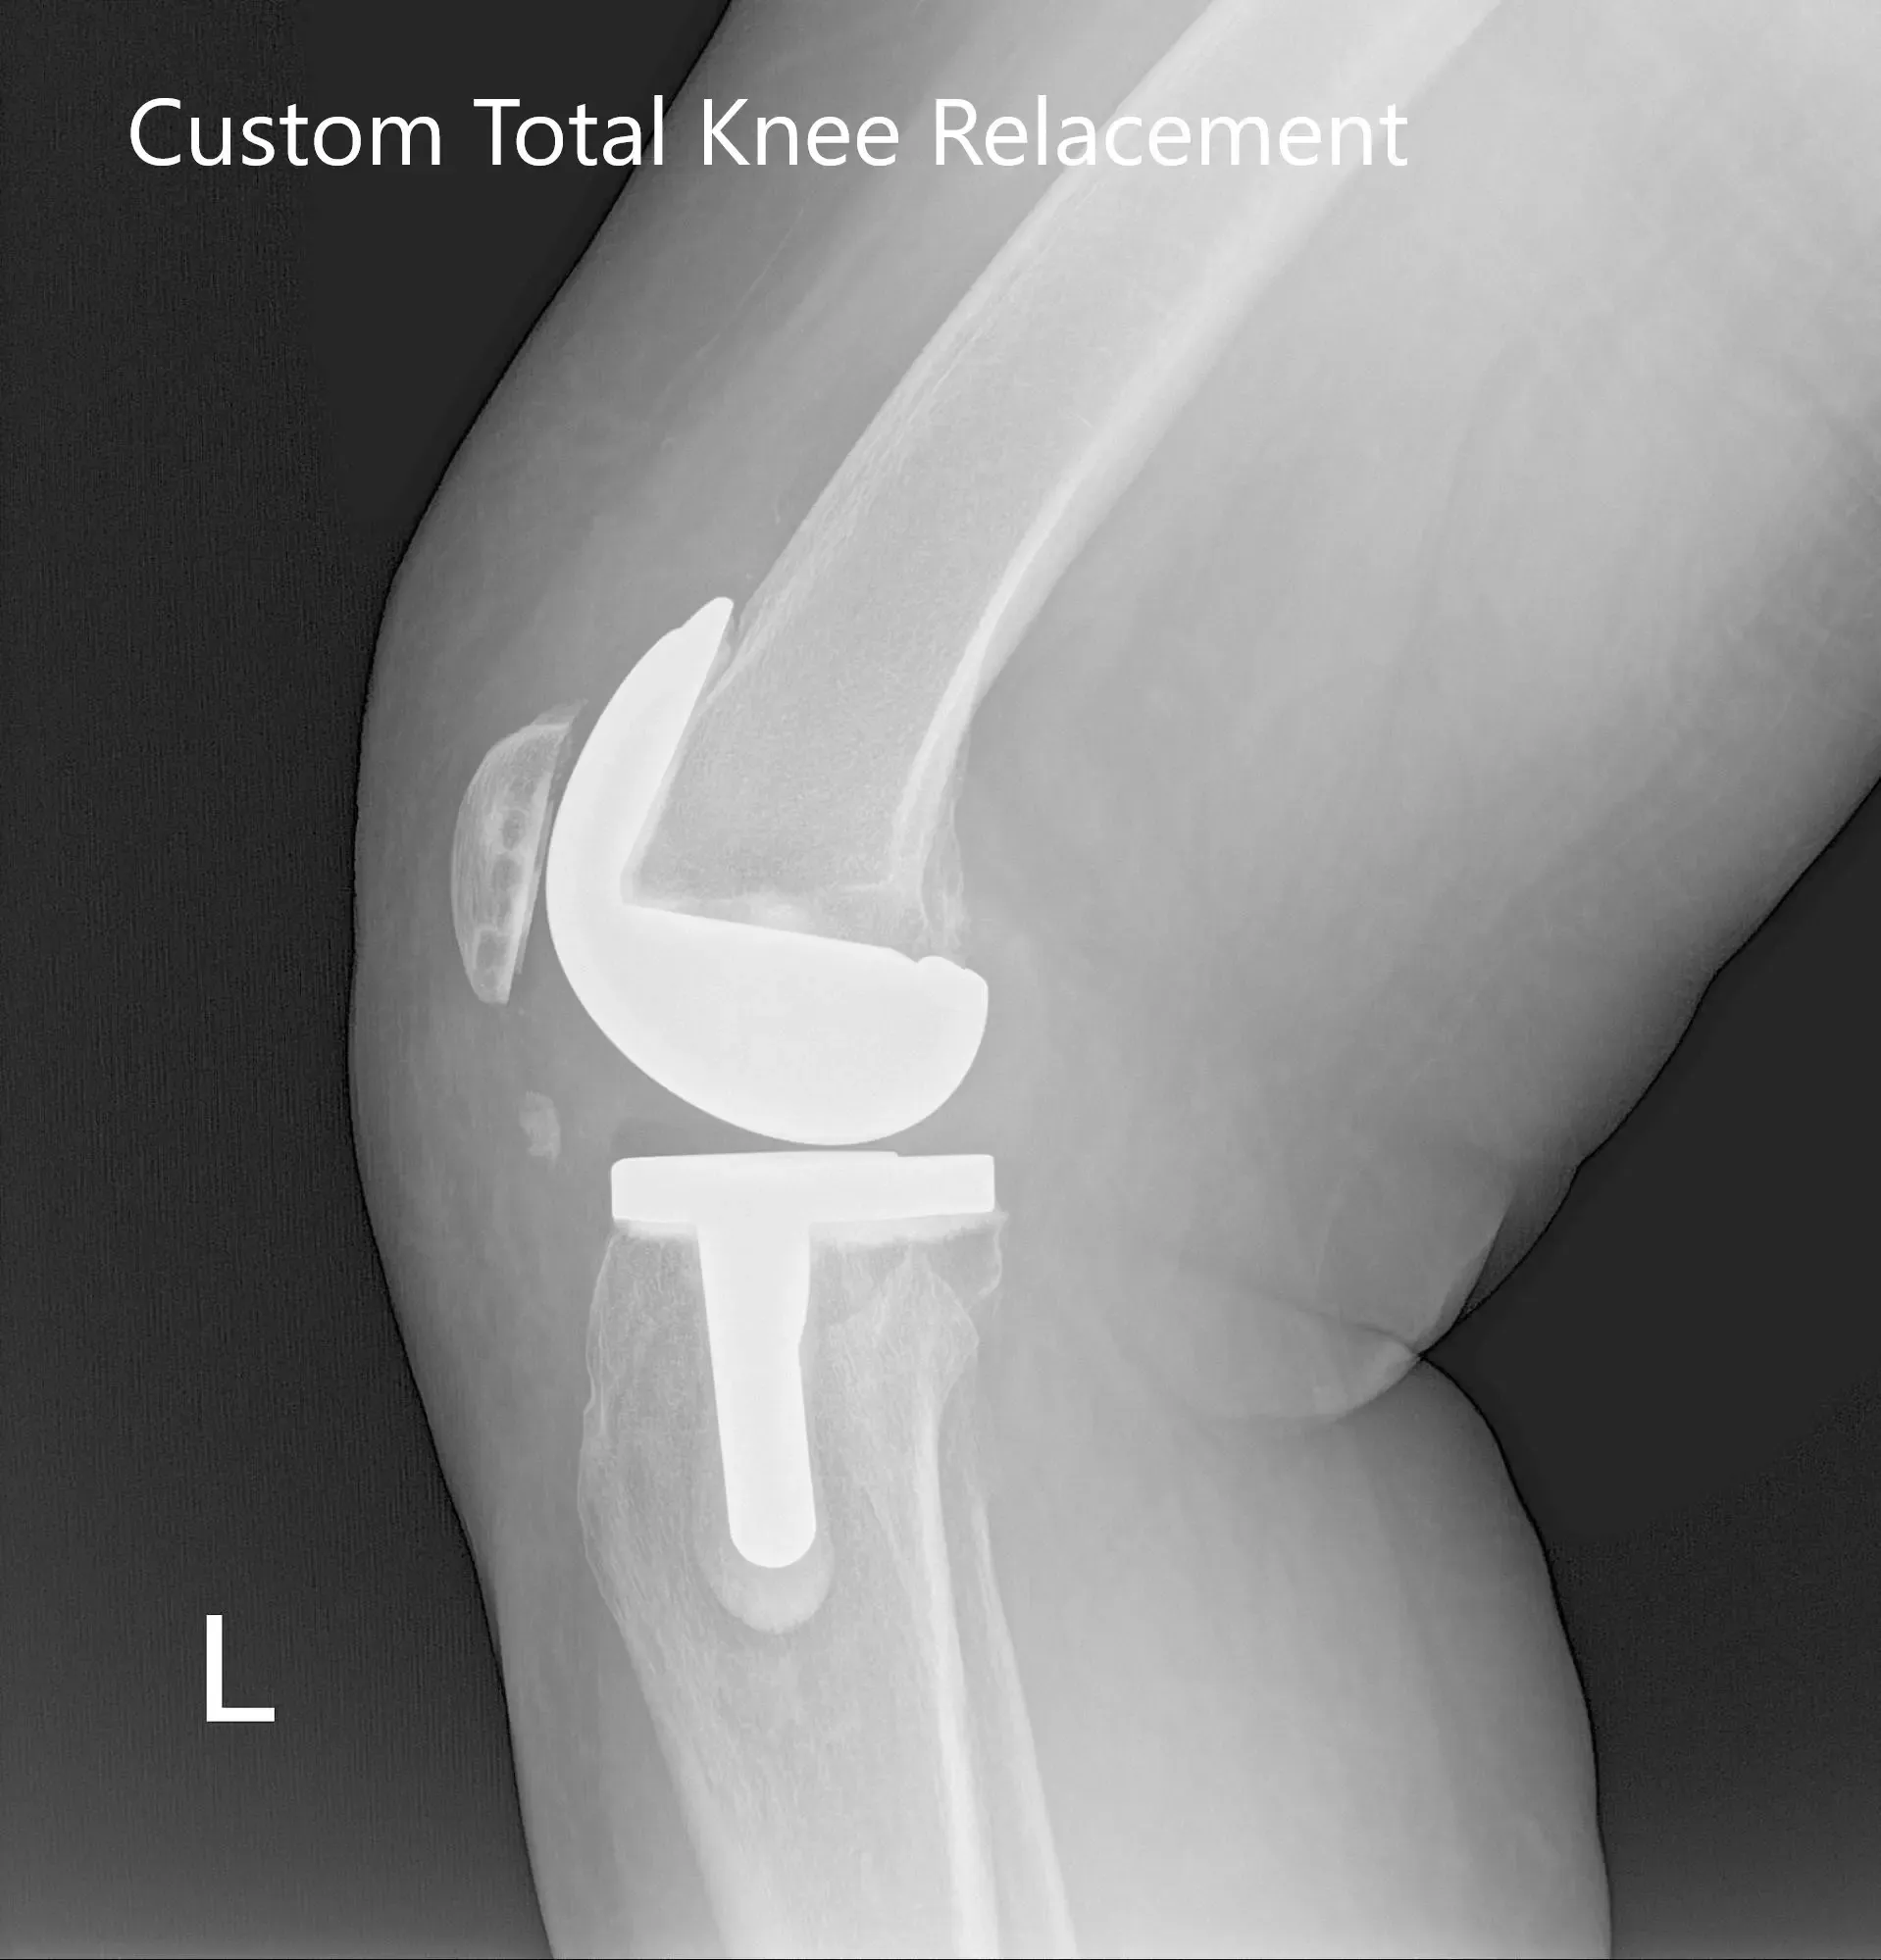

Radiografía postoperatoria de la rodilla izquierda que muestra visión AP y lateral